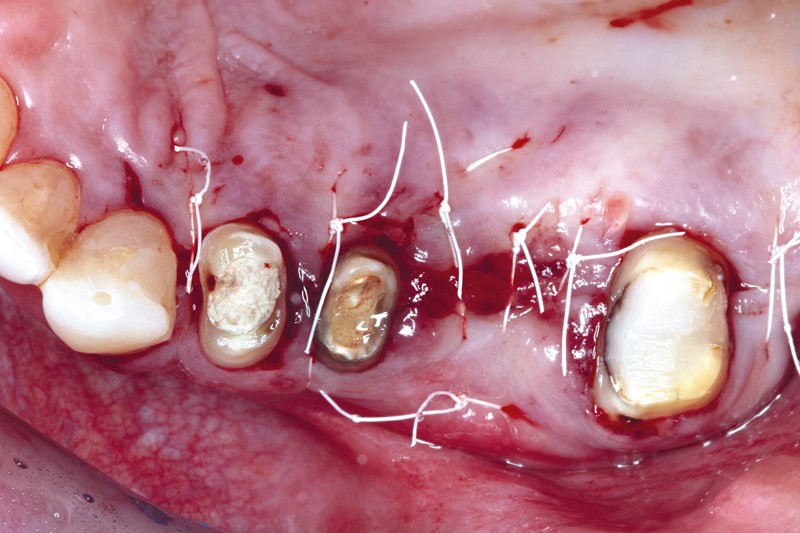

Intrabony defect treated using collprotect® membrane & cerabone® (1) - Cosgarea & Sculean

Pre-surgical probing reveals a deep intrabony defect on the distal aspect of the upper canine.